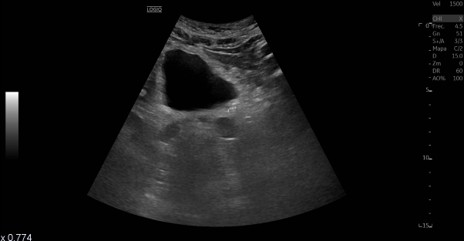

Ureterohidronefrosis grado I-II izquierda secundaria a litiasis en el uréter distal.

La ecografía se ha vuelto una herramienta clave en urgencias para valorar a los pacientes con posible cólico renal. Aunque no siempre permite ver todos los cálculos de forma directa, sí ofrece información muy útil: muestra si hay hidronefrosis, permite intuir si existe una obstrucción importante y ayuda a detectar situaciones que podrían complicar el cuadro, como una infección asociada. Su rapidez, disponibilidad y el hecho de no usar radiación la convierten en la primera prueba ideal.